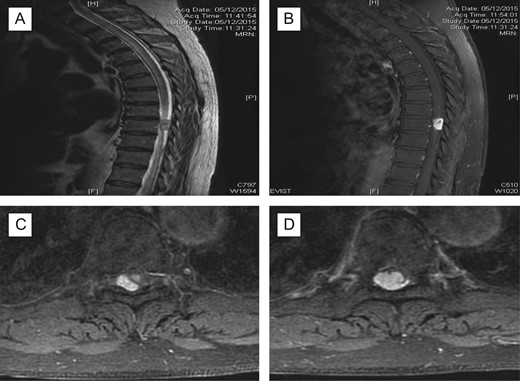

X-ray thoracolumbar spine anterior-posterior and lateral views were performed and showed slight loss of the T6 anterior vertebral height and sclerosis of the T5/T6 endplates. Mild narrowing of the T5/T6 intervertebral disc space was also seen and there were no evidence of fractures or spondylolisthesis. Magnetic resonance imaging (MRI) of the spine with contrast was then requested, showing 1.6 Ă— 1 Ă— 1.2 cm3 enhancing lesion in the spinal cord at level T9, mostly extramedullary intradural location compressing the thoracic cord with extensive cord oedema from T1 down to conus (Fig. 1). It was also suggestive of intramedullary invasion into the spinal cord, from the extramedullary enhancing mass lesion.

Pre-op MRI scan. Enhancing intraspinal lesion, most likely extramedullary intradural in location, at the level of T9 causing spinal cord compression associated with extensive cord oedema; (A) T2 sagittal; (B) with contrast, sagittal; (C, D) axial with contrast at T9 level; suggestive of intradural extramedullary (C) extending intramedullary (D).